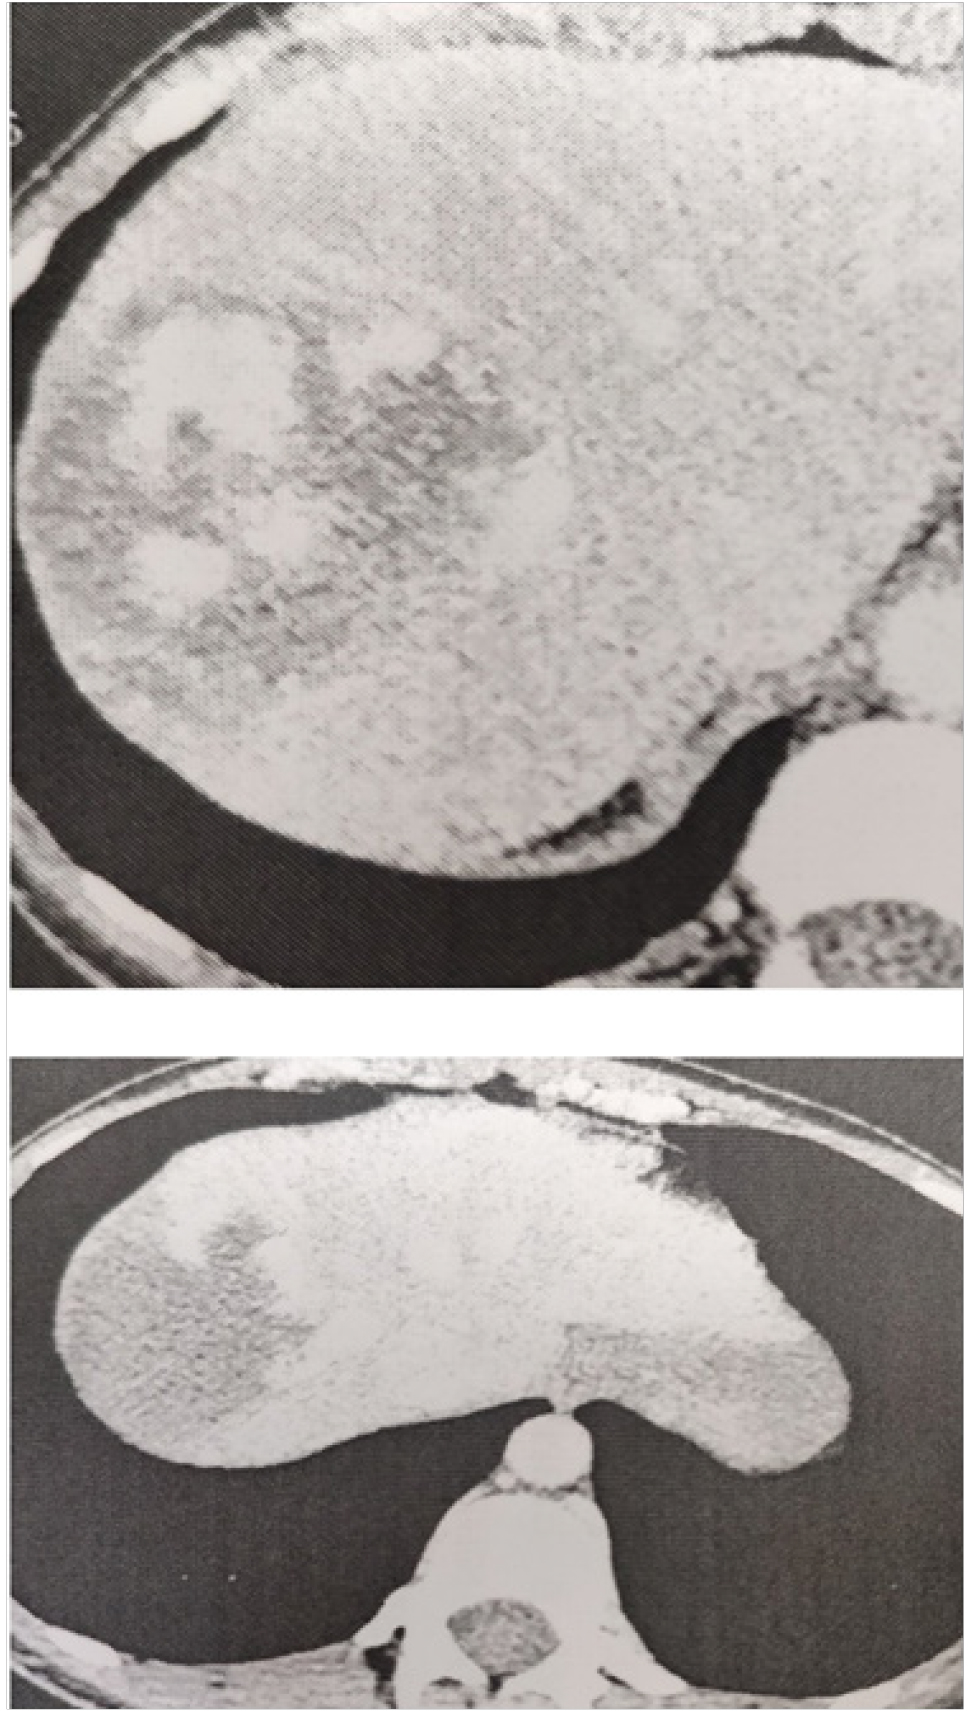

МЕТОДИКА ИССЛЕДОВАНИЯ

Рис. 1. Гемангиома 3-го и 7-го сегментов печени с типичным контрастированием